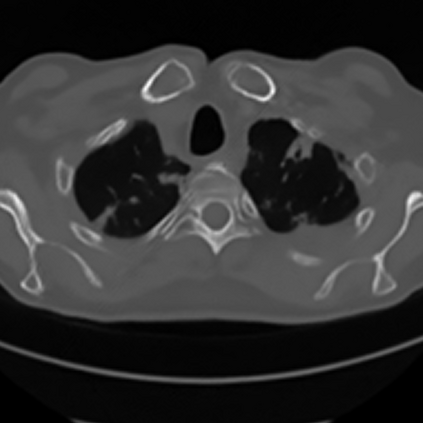

Sparse-view computed tomography (CT) -- using a small number of projections for tomographic reconstruction -- enables much lower radiation dose to patients and accelerated data acquisition. The reconstructed images, however, suffer from strong artifacts, greatly limiting their diagnostic value. Current trends for sparse-view CT turn to the raw data for better information recovery. The resultant dual-domain methods, nonetheless, suffer from secondary artifacts, especially in ultra-sparse view scenarios, and their generalization to other scanners/protocols is greatly limited. A crucial question arises: have the image post-processing methods reached the limit? Our answer is not yet. In this paper, we stick to image post-processing methods due to great flexibility and propose global representation (GloRe) distillation framework for sparse-view CT, termed GloReDi. First, we propose to learn GloRe with Fourier convolution, so each element in GloRe has an image-wide receptive field. Second, unlike methods that only use the full-view images for supervision, we propose to distill GloRe from intermediate-view reconstructed images that are readily available but not explored in previous literature. The success of GloRe distillation is attributed to two key components: representation directional distillation to align the GloRe directions, and band-pass-specific contrastive distillation to gain clinically important details. Extensive experiments demonstrate the superiority of the proposed GloReDi over the state-of-the-art methods, including dual-domain ones. The source code is available at https://github.com/longzilicart/GloReDi.